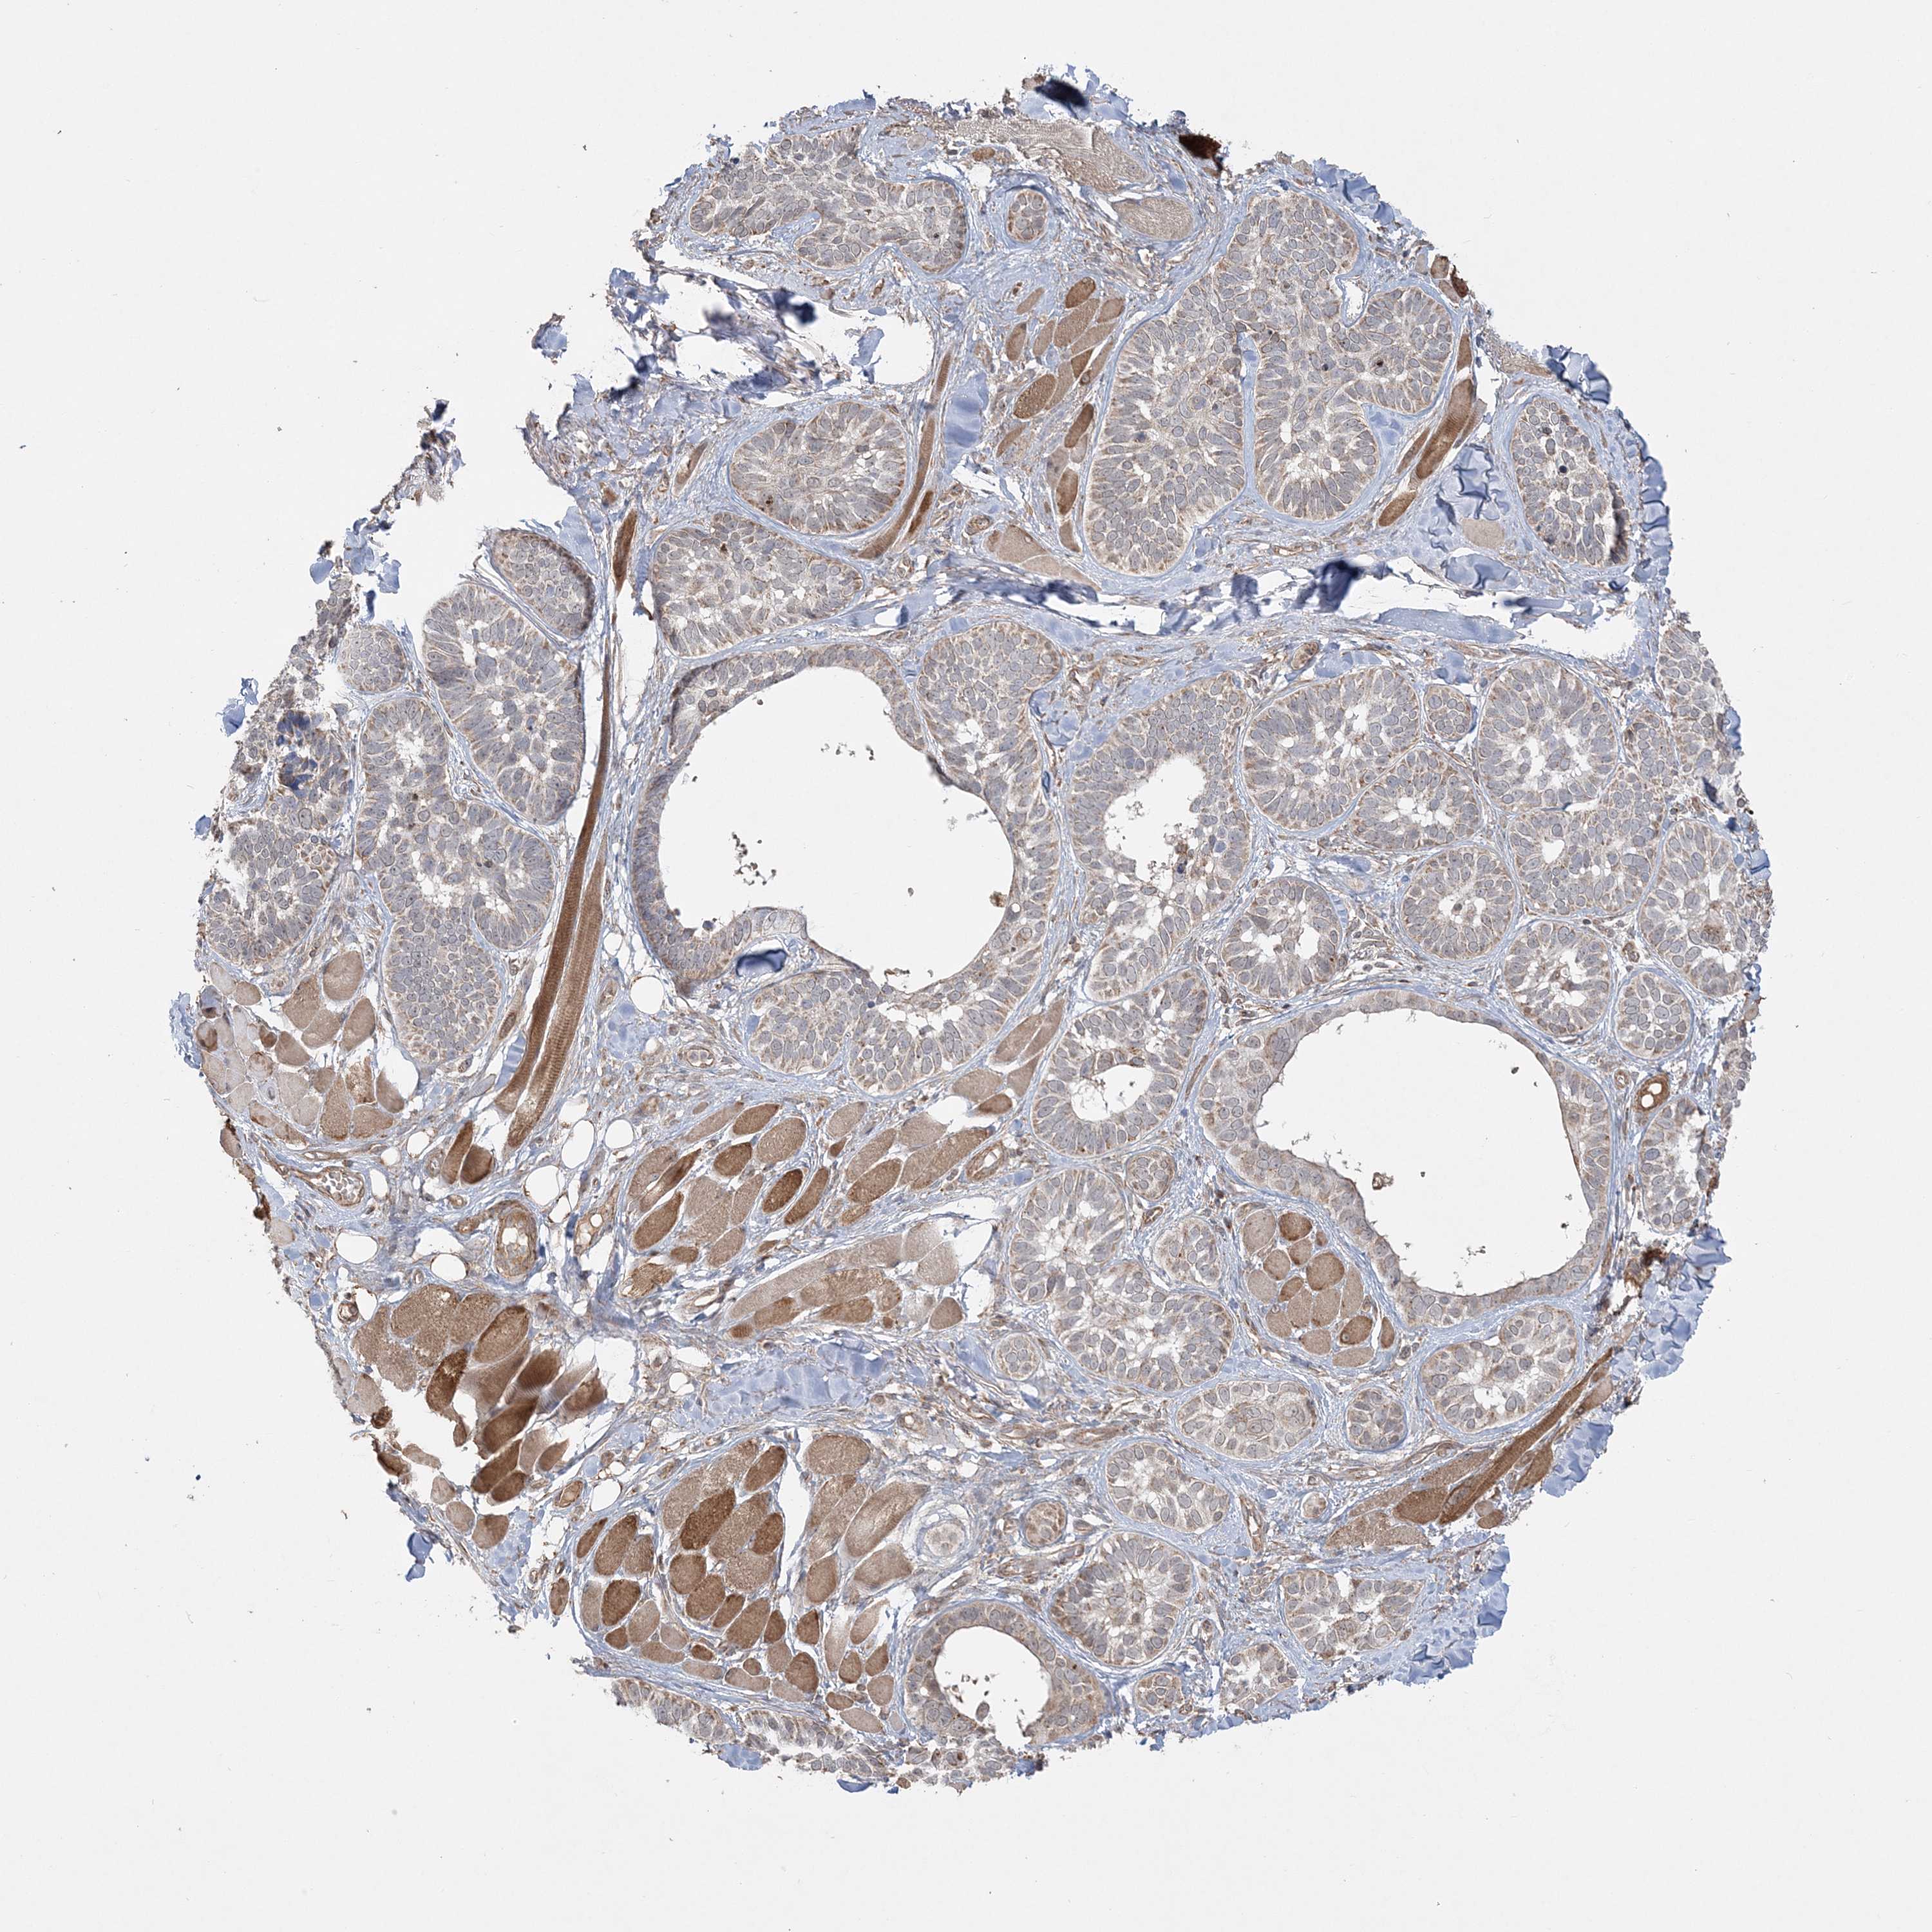

Basal cell and squamous cell cancer

SKIN CANCER - Protein expressioni

A mouse-over function shows sample information and annotation data. Click on an image to view it in a full screen mode. Samples can be filtered based on level of antibody staining by selecting one or several of the following categories: high, medium, low and not detected. The assay and annotation is described here.

Antibody stainingi

Antibody staining in the annotated cell types in the current human tissue is reported as not detected, low, medium, or high, based on conventional immunohistochemistry profiling in selected tissues. This score is based on the combination of the staining intensity and fraction of stained cells.

Each image is clickable and will lead to virtual microscopy that enables deeper exploration of all samples and also displays staining intensity scores, fraction scores and subcellular localization as well as patient and tissue information for each sample.

Antibody HPA036560

Antibody HPA036561

Staining

High

Medium

Low

Not detected

Intensity

Strong

Moderate

Weak

Negative

Quantity

>75%

75%-25%

<25%

None

Location

Nuclear

Cytoplasmic/membranous

Cytoplasmic/membranous,nuclear

Basal cell carcinoma